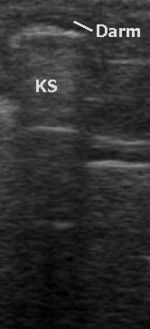

Eine aktuelle Entwicklung ist die Diagnose von Knochenbrüchen und deren Verlaufskontrolle. Insbesondere bei Brüchen im Kindesalter ist in bestimmten Regionen eine ultraschallbasierte Darstellung von Frakturen mit einer Genauigkeit möglich, die Röntgenbilder überflüssig machen kann. Zum gegenwärtigen Zeitpunkt ist der Einsatz dieser Fraktursonografie bei handgelenksnahen Unterarmfrakturen, Ellenbogen- und Oberarmbrüchen möglich.

Zugänglichkeit von Organen

Alle wasserhaltigen, blutreichen Organe sind für den Ultraschall gut untersuchbar. Schlecht untersuchbar sind alle gashaltigen oder von Knochen bedeckten Organe, zum Beispiel der Darm bei Blähungen, die Lunge, Gehirn und das Knochenmark. Manche Organe sind im Normalzustand nur schwierig, im krankhaft vergrößerten Zustand dagegen gut erkennbar (Blinddarm, Harnleiter, Nebennieren).